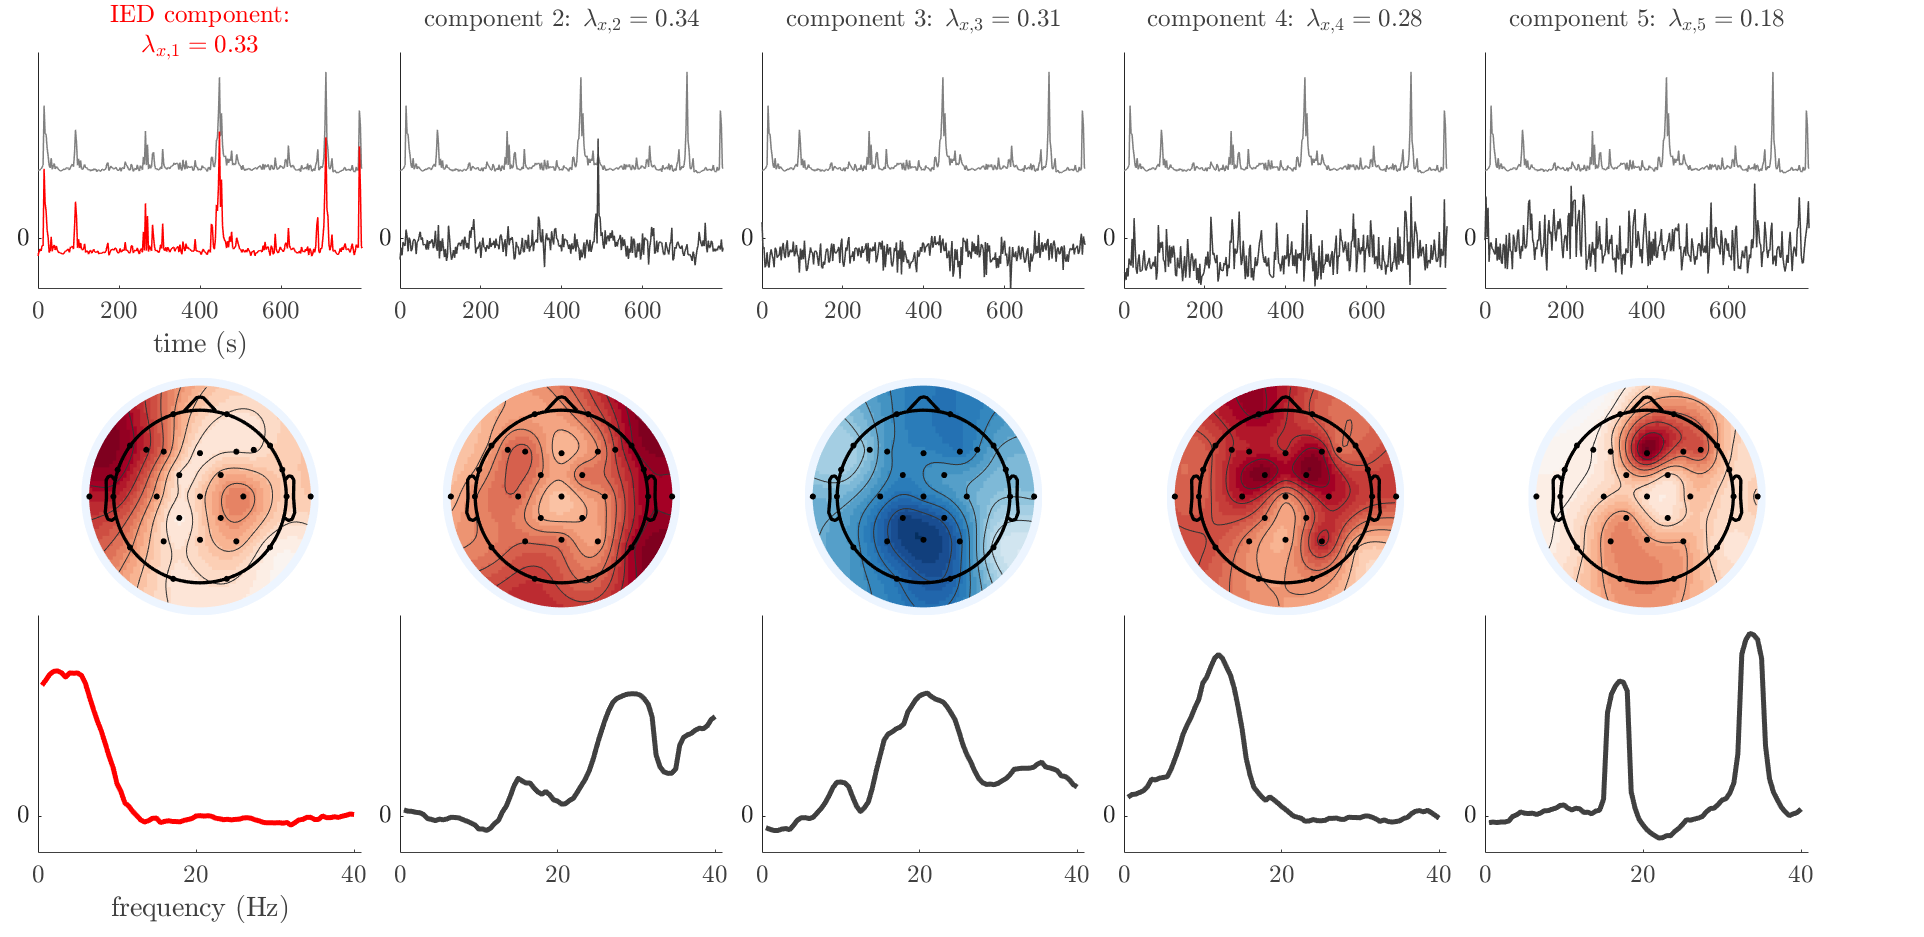

Patient 1

We analyze the solution with sources. Figure 1 shows the EEG signatures and HRF waveforms. One of the sources is highly correlated to the MWF reference (in grey), which was already known from Table B.3. This IED-related source had a typical low-frequency spectrum, which is expected for the typical spike-and-wave interictal discharges. The topography is relatively diffuse, although the highest amplitudes are mostly in the left hemisphere. This is in accordance with the lateralization of ictal onset zone (left temporal lobe, cfr. Table 1). There are some noteworthy observations to be made about some of the other components. The fourth has an unusually sharp spectrum, is mainly localized on two nonadjacent center electrodes, and is sustained for a single period of many seconds Hence, this component likely captured an artifact (of yet unknown origin), although we spotted no large-amplitude changes in the EEG itself. Similarly, the third source is only present at one frontal electrode, and exists in a frequency range above 20 Hz. It might represent a muscle artifact, e.g., due to frowning or twitching of some muscles in the forehead. The HRFs of all ROIs are shown in Figure 1(b). Two of the basis functions seem to have converged to a very similar waveform, which is an unfortunate possibility if two initial HRFs are too close to the same local optimum in their respective parameters. This reduces the expressive power of the basis set, which is clearly visible, since many ROIs have a nearly identical HRF. One of the twenty ROIs with the highest-entropy HRF overlapped the IOZ, although clearly this HRF (bold line) is not among the most dissimilar waveforms for this patient. This is also visible in Figure 2: both the HRF entropy and extremity maps show a small overlap with the delineated IOZ. Despite the good correspondence in the EEG domain, no significant (de)activation of the IED-component is found inside the IOZ.